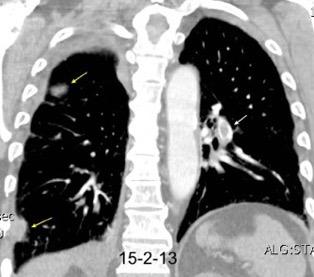

Tromboembolismo pulmonar.

Frecuencia del derrame:

Rx: 32%. TC: 47%

Unilateral. 85%

< 1/3 del hemitórax: 90%

Todos exudados

58% con eritrocitos

21% tabicación lo que causa demora en el diagnóstico

TEP. Empiema pleural. Atelectasia redonda

Porcel JM et al. Analysis of pleural effusions in acute pulmonary embolism: radiological and pleural fluid data from 230 patients. Respirology 2007/ Iguchi T et al. Desquamation of the subpleural lung parenchyma caused by empyema after pulmonary embolism: A case report. Respirol Case Rep. 2022 .